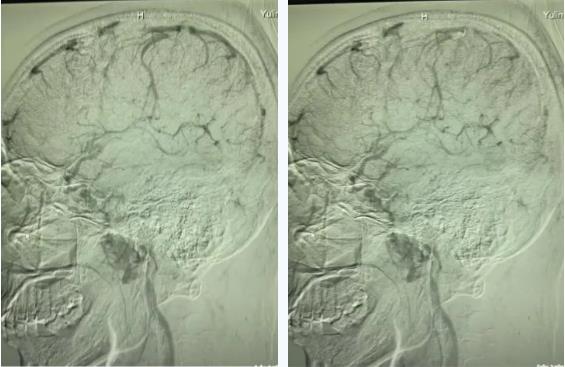

患者脑血管造影图片

近日,交大一附院榆林医院神经重症医学科带头人汪杰教授团队成功救治一名自身免疫性脑炎继发颅内静脉窦血栓形成患者,该患者现已出院。吴先生(化名)10余天前无诱因出现头痛,右侧颞部及枕部闷胀痛,平躺加重、活动稍缓解,外院就诊未缓解且加重后到交大一附院榆林医院急诊医学科就诊。经急诊医学科救治后,患者自觉病情好转,要求回家观察。神经重症医学科汪杰教授会诊时查看CT,认为患者不排除静脉窦血栓的可能性,遂与患者及家属进行充分沟通,详细分析患者可能面临的病情风险及进一步检查的利弊,建议完善头颅核磁共振检查。患者及家属在了解情况后,决定完善头颅核磁平扫及磁共振静脉成像(MRV),显示:右侧横窦、乙状窦、上矢状部分窦信号缺失,考虑静脉窦血栓形成,遂急诊行脑血管造影,确诊颅内静脉窦血栓形成(上矢状窦、直窦、横窦),给予抗凝、降颅压、预防癫痫治疗。